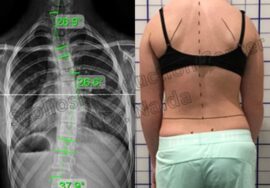

السبب الرئيسي لزيادة الانحناء هو النمو السريع. فعندما يدخل الطفل أو المراهق مرحلة النمو، خصوصًا بين عمر 10 و15 سنة، يبدأ العمود الفقري في التمدد بسرعة، وهنا يمكن أن يتفاقم الانحناء إذا لم تتم المتابعة الصحيحة.

إجراء أشعة متابعة بانتظام لمراقبة زاوية الانحناء (زاوية كوب).

الأطفال قد لا يشتكون كثيرًا، لكن هناك علامات يجب ألا يتجاهلها الأهل:

بروز الضلوع

ارتفاع كتف عن الآخر

ميل الحوض

عدم انتظام الخصر

ألم متكرر في الظهر

هذه قد تكون إشارات على زيادة زاوية الانحناء، ويجب مراجعة الطبيب فورًا.